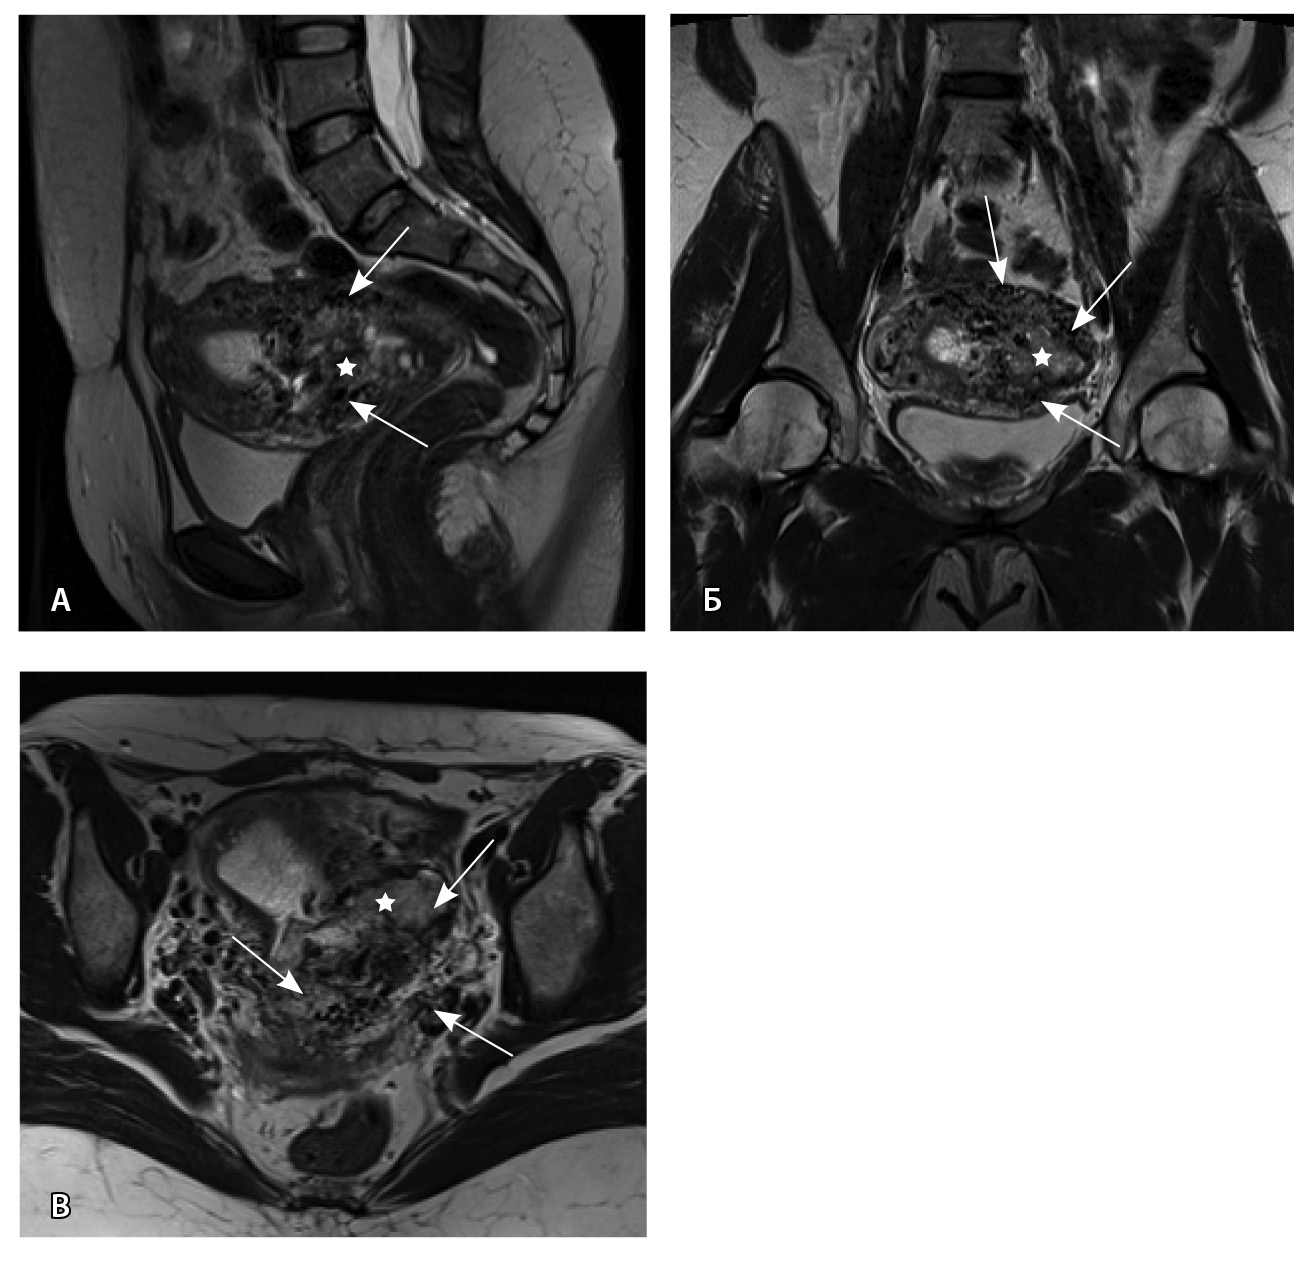

Пациентке выполнено МРТ-исследование на МР-томографе Siemens MAGNETOM Verio с индукцией магнитного поля 3T, с использованием стандартных катушек, в режимах Т1-взвешенного изображения (ВИ), Т2-ВИ, Т2-FS, FIESTA, DWI с получением изображений в сагиттальной, корональной и аксиальной плоскостях, динамическое внутривенное контрастирование (гадопентетовая кислота 0,2 мл/кг массы тела). Матка увеличена в размерах, с признаками снижения зональной дифференциации стенок, усиленным сосудистым компонентом, полость матки расширена с наличием примеси геморрагического содержимого, неравномерным утолщением эндометрия и пристеночными компонентами слизистой. В нижнем маточном сегменте определяется несостоятельный рубец от кесарева сечения, с наличием участка резко истонченной пролабирующей стенки матки слева и наличием дополнительного образования неоднородного сигнала, суммарно до 4,0 × 2,3 × 3,2 см, представленного фрагментами мягкотканного хориона (изоинтенсивного на Т2-ВИ), достигающего серозного покрова матки, и патологического сосудистого компонента в виде расширенных полнокровных сосудов, зон неоангиогенеза (рис. 1). На DWI признаков ограничения диффузии не определялось.

Рис. 1. Остатки вросшего хориона в несостоятельный рубец от кесарева сечения. Магнитно-резонансная томограмма, Т2-взвешенное изображение в сагиттальной (А), корональной (Б), аксиальной (В) плоскостях. Признаки наличия в проекции несостоятельного рубца от кесарева сечения фрагментов ткани вросшего хориона изоинтенсивного сигнала (отмечен звездочкой), с распространением до серозного покрова матки. Стрелками указаны гипоинтенсивные сосуды, зоны неоангиогенеза, артериовенозные сосудистые коллатерали